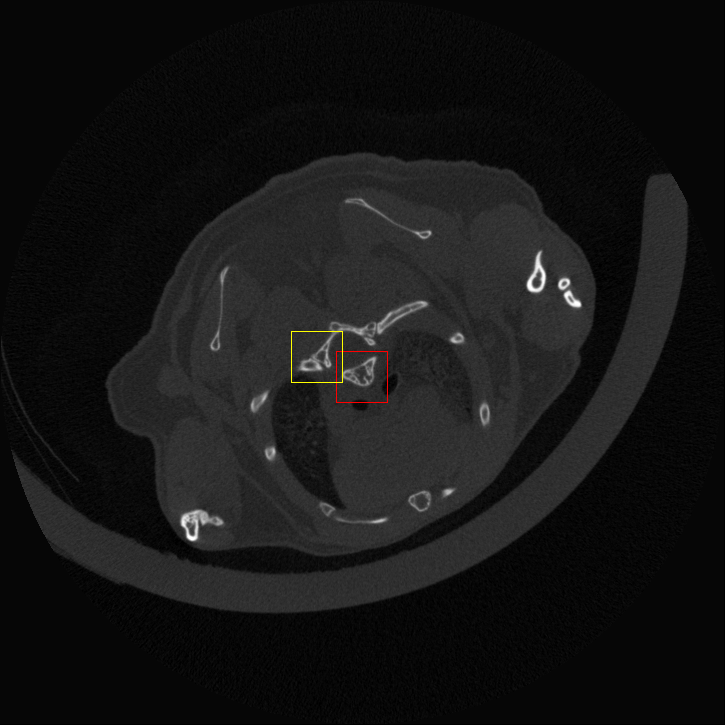

Figure 4: Visual comparsion of SRCT Case 111 from the Tibia dataset. The restored bony structures are shown in the red and yellow boxes in Fig. 5. The display window is [-900, 2000] HU.

Figure 5: Zoomed regions of interest (ROIs) marked by the red rectangle in Fig. 4. The restored image with GAN-CIRCLE reveals subtle structures better than the other variations of the proposed neural network, especially in the marked regions. The display window is [-900, 2000] HU.

III-D Experimental Results with the Tibia Dataset

We evaluated the proposed algorithms against the state-of-the-art algorithms on the tibia dataset. We present typical results in Fig. 4. It is observed that BM3D can effectively remove the noise, but it over-smoothens the noisy LR images. Then, the interpolation-based methods (NN+, Bilinear+, Bicubic+, Lanczos+) yield noticeable artifacts caused by partial aliasing. On the other hand, the DL-based methods suppress such artifacts effectively. It can be seen that our proposed GAN-CIRCLE recovers more fine subtle details and captures more anatomical information in Fig. 5. It is worth mentioning that Fig. 4 shows that there are severe distortions of the original images but SRGAN generates compelling results in Figs. 6-8, which indicate VGG network is a task-specific network which can generate images with excellent image quality. We argue that the possible reason is that the VGG network [68] is a pre-trained CNN-based network based on natural images with structural characteristic correlated with the content of medical images [80]. Fig. 5 presents that the proposed GAN-CIRCLEs can predict images with shaper boundaries and richer textures than GAN-CIRCLE, and GAN-CIRCLEu which learns additional anatomical information from the unpaired samples. The quantitative results are in Table II. The results demonstrate that the G-Forward achieves the highest scores using the evaluation metrics, PSNR and SSIM, which outperforms all other methods. However, it has been pointed out in [81, 82] that high PSNR and SSIM values cannot guarantee a visually favorable result. Non-GAN based methods (FSRCNN, ESPCN, LapSRN) may fail to recover some fine structure for diagnostic evaluation, such as shown by zoomed boxes in Fig. 5. Quantitatively, GAN-CIRCLE achieves the second best values in terms of SSIM and IFC. It has been pointed out in [83] that IFC value is correlated well with the human perception of SR images. Our GAN-CIRCLEs obtained comparable results qualitatively and quantitatively. Table II shows that the proposed semi-supervised method performs similarly compared to the fully supervised methods on the tibia dataset. In general, our proposed GAN-CIRCLE can generate more pleasant results with sharper image contents.